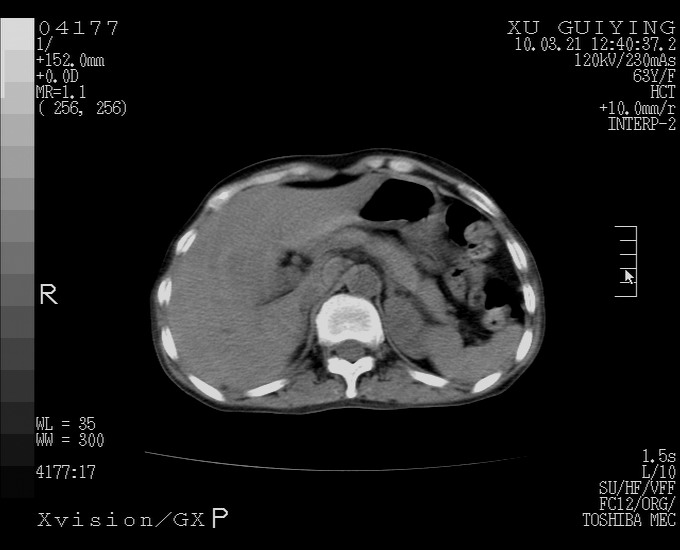

怎么没有增强呢?胆囊那么大,密度有些高啊。

慢性胆囊炎,胆囊占位不排除,建议增强或彩超。

考虑胆囊炎 不除外泥沙样结石

胆囊体积增大,胃窦壁增厚

胆囊体积增大

胆囊体积增大,密度不均匀,结石不除外;胃壁增厚,考虑胃癌,建议增强。

胆囊体积增大 ,建议超声检查。

胆囊体积增大,密度增高,较均匀,外缘也较光滑,应考虑胆囊炎。因为胃未充盈,不好说壁增厚。肝左叶及脾门处见低密度灶,有可能是血管瘤,不排除囊肿。建议超声检查或强化。

胆囊增大,原因待查。